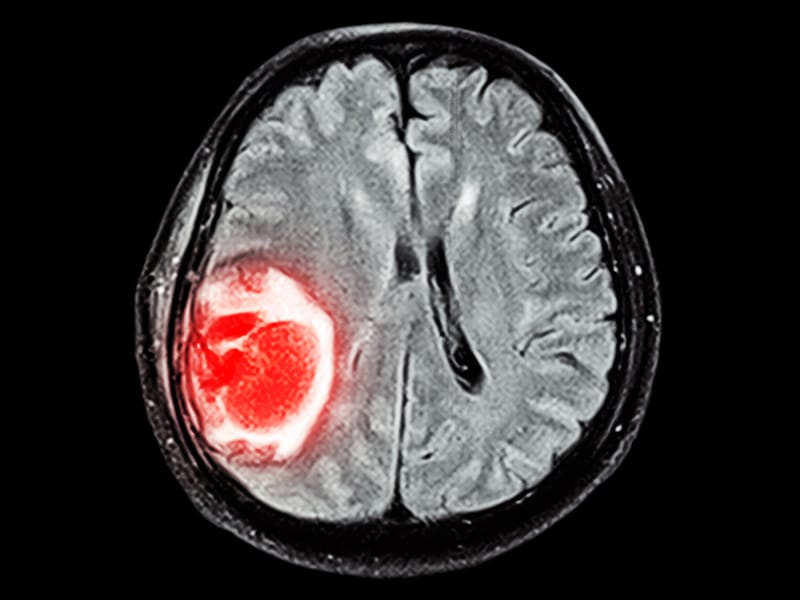

Kernstück der Diagnostik sind bildgebende Verfahren, wobei die Kernspintomographie (MRT) der Computertomographie (CT) überlegen ist.

Die Computertomographie spielt als schnell durchführbares und breit verfügbares Verfahren vor allem eine Rolle in der Notfallmedizin. Größere Metastasen grenzen sich als hypodense oder selten (Malignes Melanom, Chorionkarzinom) hyperdense Struktur gegen das normale Hirnparenchym ab. Da Metastasen aber auch isodens sein können, ist womöglich nur die raumfordernde Wirkung als Massenverschiebung oder die hypodense Formation des Perifokalödems abgrenzbar. Zentrale Einblutungen, wie sie insbesondere bei Metastasen von malignen Melanomen oder Nierenzellkarzinomen vorkommen, sind in der CT gut nachweisbar. In Abhängigkeit von der gewählten Schichtdicke liegt die Nachweisgrenze bei etwa einem Zentimeter, so dass kleinere Metastasen der nativen Computertomographie entgehen können.

Da die Computertomographie einen relativ geringen Weichteilkontrast aufweist, ist die Gabe von Kontrastmittel entscheidend: aufgrund der Störung der Blut-Hirn-Schranke im Bereich der Metastase kommt es zur Anreicherung von Kontrastmittel (Enhancement), das bei Vorliegen einer zentralen Nekrose häufig ring- oder girlandenförmig erscheint.

Kernspintomographie

Die Kernspintomographie weist bei besserer Weichteildifferenzierung, insbesondere nach Gabe von Gadolinium als Kontrastmittel, eine deutlich höhere Sensitivität auf und ist somit geeigneter für die Suche nach Hirnmetastasen. So ist im Vergleich zur CT-Untersuchung die Rate der Patienten mit im MRT nachgewiesenen Hirnmetastasen mehr als doppelt so hoch. Das gilt besonders für sehr kleine Befunde und Metastasen im Bereich der hinteren Schädelgrube. Die Kernspintomographie kann zur Abgrenzung gegen Hirnabszesse oder andere möglicherweise ähnlich imponierende Läsionen um eine Kernspinresonanzspektroskopie ergänzt werden.